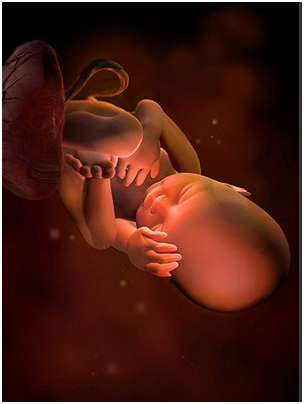

怀孕第27周从现在开始,你的宝宝会经常打嗝,每一次持续几分钟,好好地享受这些有趣的时刻吧!这...

怀孕第27周从现在开始,你的宝宝会经常打嗝,每一次持续几分钟,好好地享受这些有趣的时刻吧!这... -

怀孕第28周胎儿图 从现在开始,你就进入了孕晚期,要注意的事情很多呦!你要每天做胎动...

怀孕第28周胎儿图 从现在开始,你就进入了孕晚期,要注意的事情很多呦!你要每天做胎动... -

怀孕第29周现在你能明显地感觉到宝宝的胎动了,如果你注意到胎动有所减少,要让你的医生知道哦!...

怀孕第29周现在你能明显地感觉到宝宝的胎动了,如果你注意到胎动有所减少,要让你的医生知道哦!... -

怀孕第30周你一直在给宝宝讲故事、唱歌吗?如果是的,那么现在的宝宝已经非常熟悉你的声音了!这...

怀孕第30周你一直在给宝宝讲故事、唱歌吗?如果是的,那么现在的宝宝已经非常熟悉你的声音了!这... -

怀孕第31周这周宝宝的眼睛时开时闭,他大概能够看到子宫里的景象了!你可能时常会感到呼吸越发困...

怀孕第31周这周宝宝的眼睛时开时闭,他大概能够看到子宫里的景象了!你可能时常会感到呼吸越发困... -

怀孕第32周这个时候,你一定要坚持每两周一次的体检,检查时要注意脐带的扭转情况。最近你可能会...

怀孕第32周这个时候,你一定要坚持每两周一次的体检,检查时要注意脐带的扭转情况。最近你可能会... -